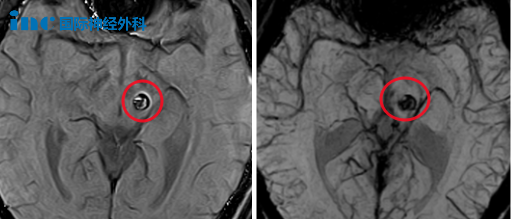

2023年6月23日,小林第1次出血

術前術后MRI影像